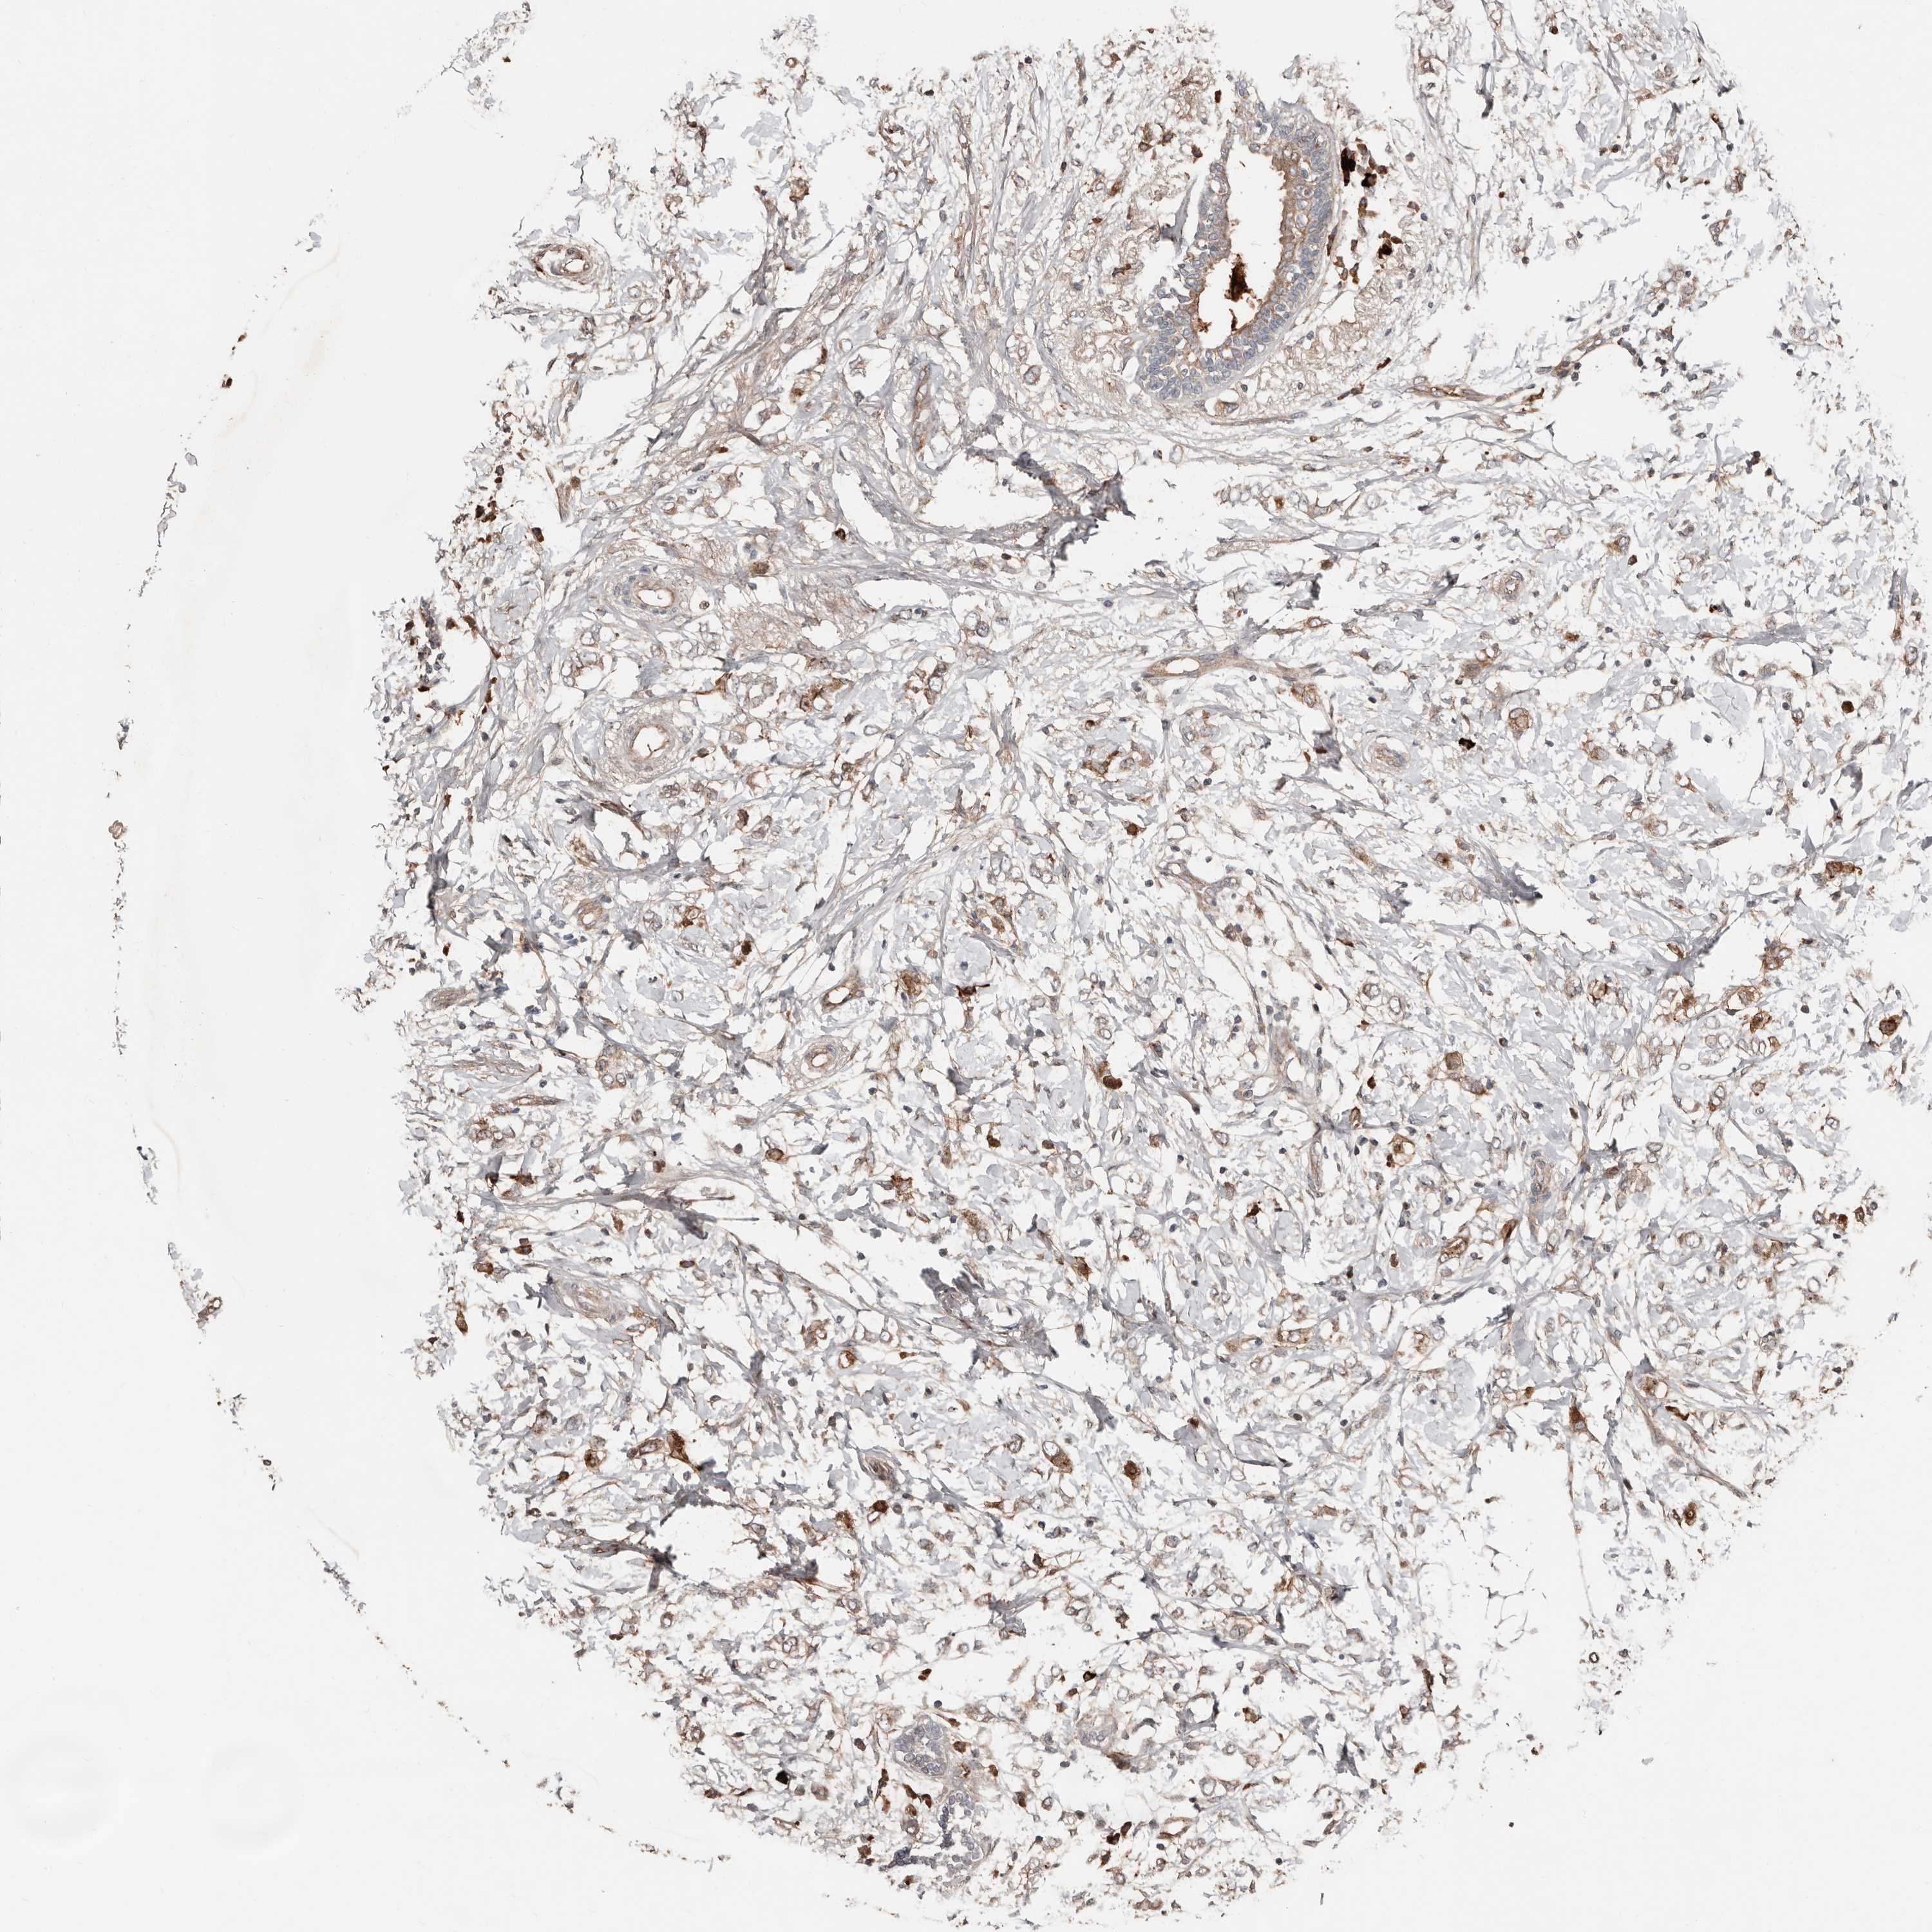

BRCA TCGA BRCA VALIDATION PROTEIN EXPRESSION

ANTIBODIES

AND

VALIDATION